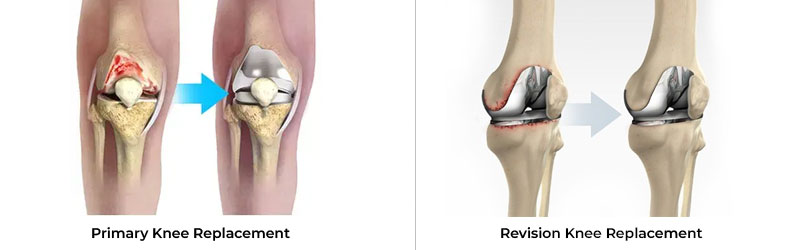

Primary Knee Replacement and Revision Knee Replacement are surgical procedures related to the knee joint, commonly performed to relieve pain and restore function in patients with severe arthritis or knee damage.

Primary knee replacement is the first surgery a patient undergoes to replace a damaged or worn-out knee joint. It is typically performed for conditions like osteoarthritis, rheumatoid arthritis, or traumatic injury to the knee joint.

Revision knee replacement is a more complex procedure done when a previously implanted knee prosthesis fails or wears out. It involves removing the old prosthetic components and replacing them with new ones.

Both procedures aim to restore function, reduce pain, and improve the patient's quality of life, but revision knee replacement is typically performed after a primary replacement fails or develops complications.